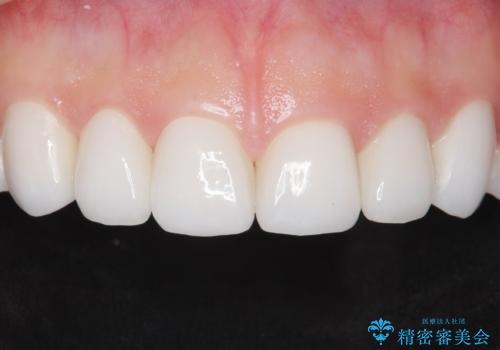

[セラミック治療] 前歯の見た目をきれいにしたい

担当医 大元洋佑

![[セラミック治療] 前歯の見た目をきれいにしたいの症例 治療後](https://seimitsushinbi.jp/wp/wp-content/uploads/2021/06/06be0471d173ef54e4277b1c3034407c-500x350.jpg?v=1622871768)